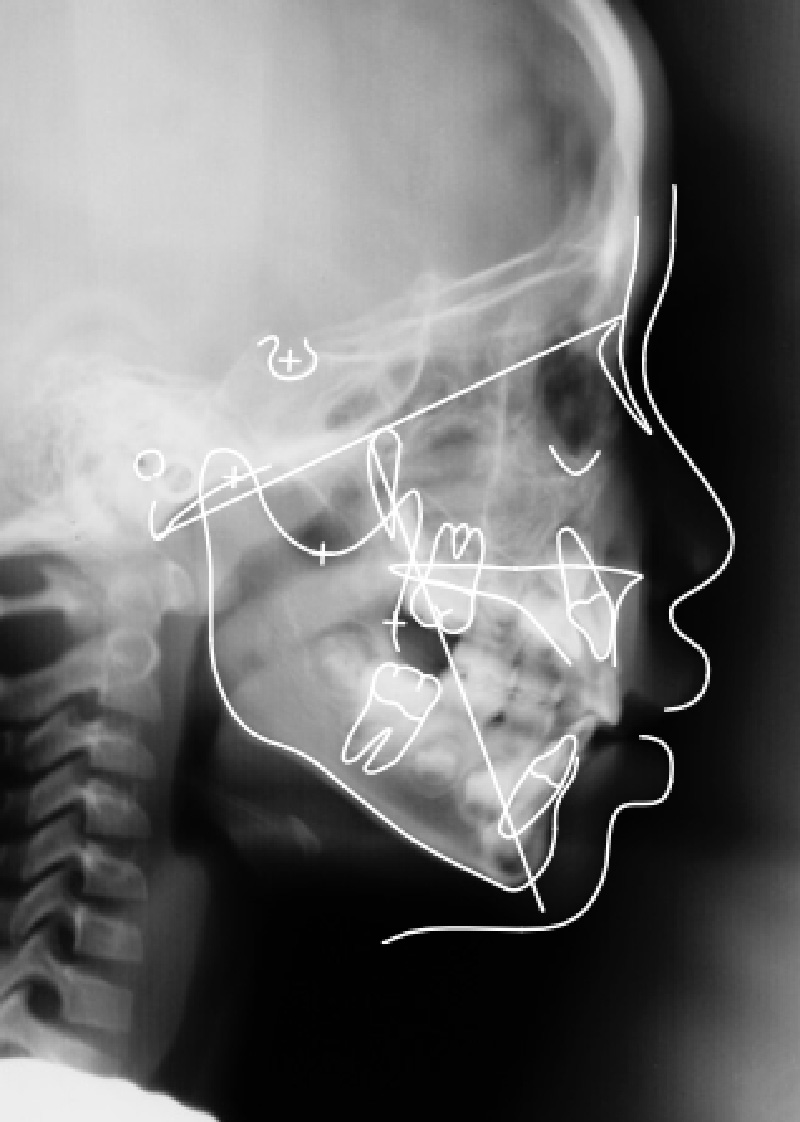

頭部X線規格写真

スプリント療法後、オトガイの左側への偏位が改善しています。下顎枝の長さも左右ほぼ同等の長さになっています。

オトガイの左側への偏位が改善しています。下顎枝の長さも左右ほぼ同等の長さになりました。